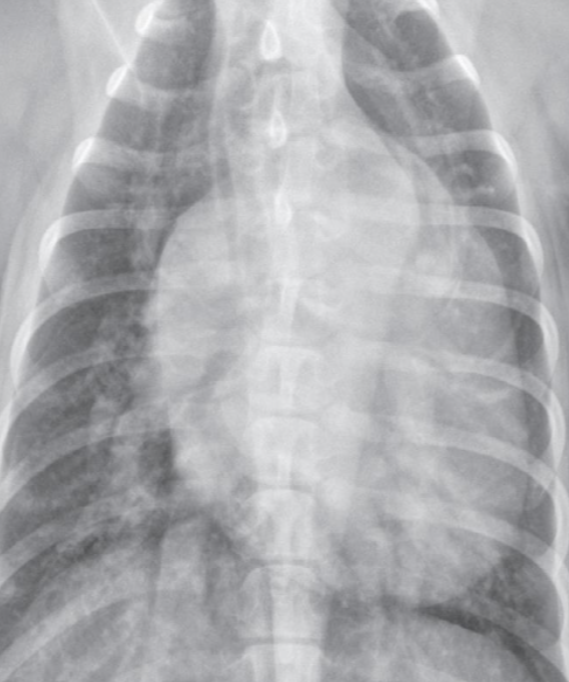

Pulmonic stenosis, Pulmonic hypertension

| PS | PH (โ HW) | |

|---|---|---|

| ํ๋๋งฅ ํ์ฐฉ์ฆ. ํ๋ง์ด ์ข์์ง๋ ์งํ. ์ข์์ง ๋ถ์์ ๋ค์ ๋ถ๋ถ์ด ํ๋ฅ๋ก ์ธํด ์๊ทน๋์ด ํ์ฅ. ํ์ก์ ๋ด๋ณด๋ด๊ธฐ ์ํด ์ฐ์ฌ์ค ์๋ ฅ ์ฆ๊ฐ, ๋น๋. ์ฐ์ฌ๋ฐฉ โ ์ฐ์ฌ์ค๋ก์ ํ๋ฅ ์ฅ์ ๋ก ์ธํด ์ฐ์ฌ๋ฐฉ๋ ๋น๋. | ์ฃผ ์์ธ์ ์ฌ์ฅ์ฌ์์ถฉ. - ๋ง๋จ ํ๋๋งฅ์ด ๋๊บผ์์ง๊ณ , ๊ตฌ๋ถ๊ตฌ๋ถํด์ง. - ํ๋๋งฅ ์๋ ฅ ์์น โ RV hypertrophy โ RA enlargement | |

| Radiographic sign - mPA bulging (1์ ๋ฐฉํฅ) : Reversed D - RVE, RAE - post-stenotic dilation : ๊ตญ์์ ์ผ๋ก ๋ฐ์, ๋ง๋จ ํ๊ด์ ์ ์ - ํ๋๋งฅ์ ์ ์์ธ ๊ฒ์ด ํน์ง (PH๋ ํ๋๋งฅ ์ปค์ง) | Radiographic sign - mPA ํ์ฅ โ Reversed D sign - RV hypertrophy - Pulmonary artery enlargement, tortuosity - RCHF์์์ฒ๋ผ Hepatomegaly, ascites, pleural effusion | |

![]() | ![]() | |

![]() | ![]() |